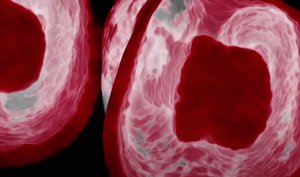

Hierzu stehen heute der modernen Zahnheilkunde vielfältige Technologien zur Verfügung, um die Zähne endodontisch zu diagnostizieren. Neben der 2D-Radiologie und Mikroskopie ist die DVT-Technologie das wichtigste Diagnosewerkzeug.

Die byzzEz3D-i Software mit dem erweiterbaren Endo-Modul rekonstruiert aus den ultra-hochauflösenden Schichtaufnahmen perfekte 3D-Aufnahmen. Die 3D-Endo-Aufnahmen können als Hologramm in allen drei Dimensionen vermessen werden. Sowohl die Bi- und Trifurkation, Kanalanzahl, Kanalverlauf, Kanallänge und -durchmesser sowie die Krümmungsradien können einfach farblich gekennzeichnet werden. Damit ist das 3D-Endo-Modul nicht nur ein ideales Instrument zur Vorbereitung für die Wurzelkanalaufbereitung und WSR, sondern auch ein hervorragendes Hilfsmittel zur 3D-Visualisierung, Behandlungsplanung und Patientenberatung.